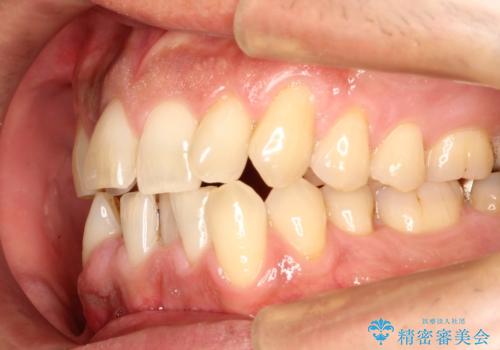

インビザライン invisalign ガタつきを治すマウスピース矯正

- 非抜歯・上顎臼歯遠心移動によるマウスピース矯正を計画した。

ガタつきを取り除くだけであれば非常に簡潔であるマウスピース矯正ですが、奥歯の位置関係の是正や、垂直的な歯の位置のコントロールなどが計画に含まれる場合、治療が難しくなってきます。